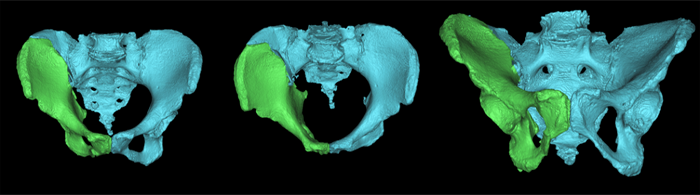

术前CT三维重建

人工智能手术规划